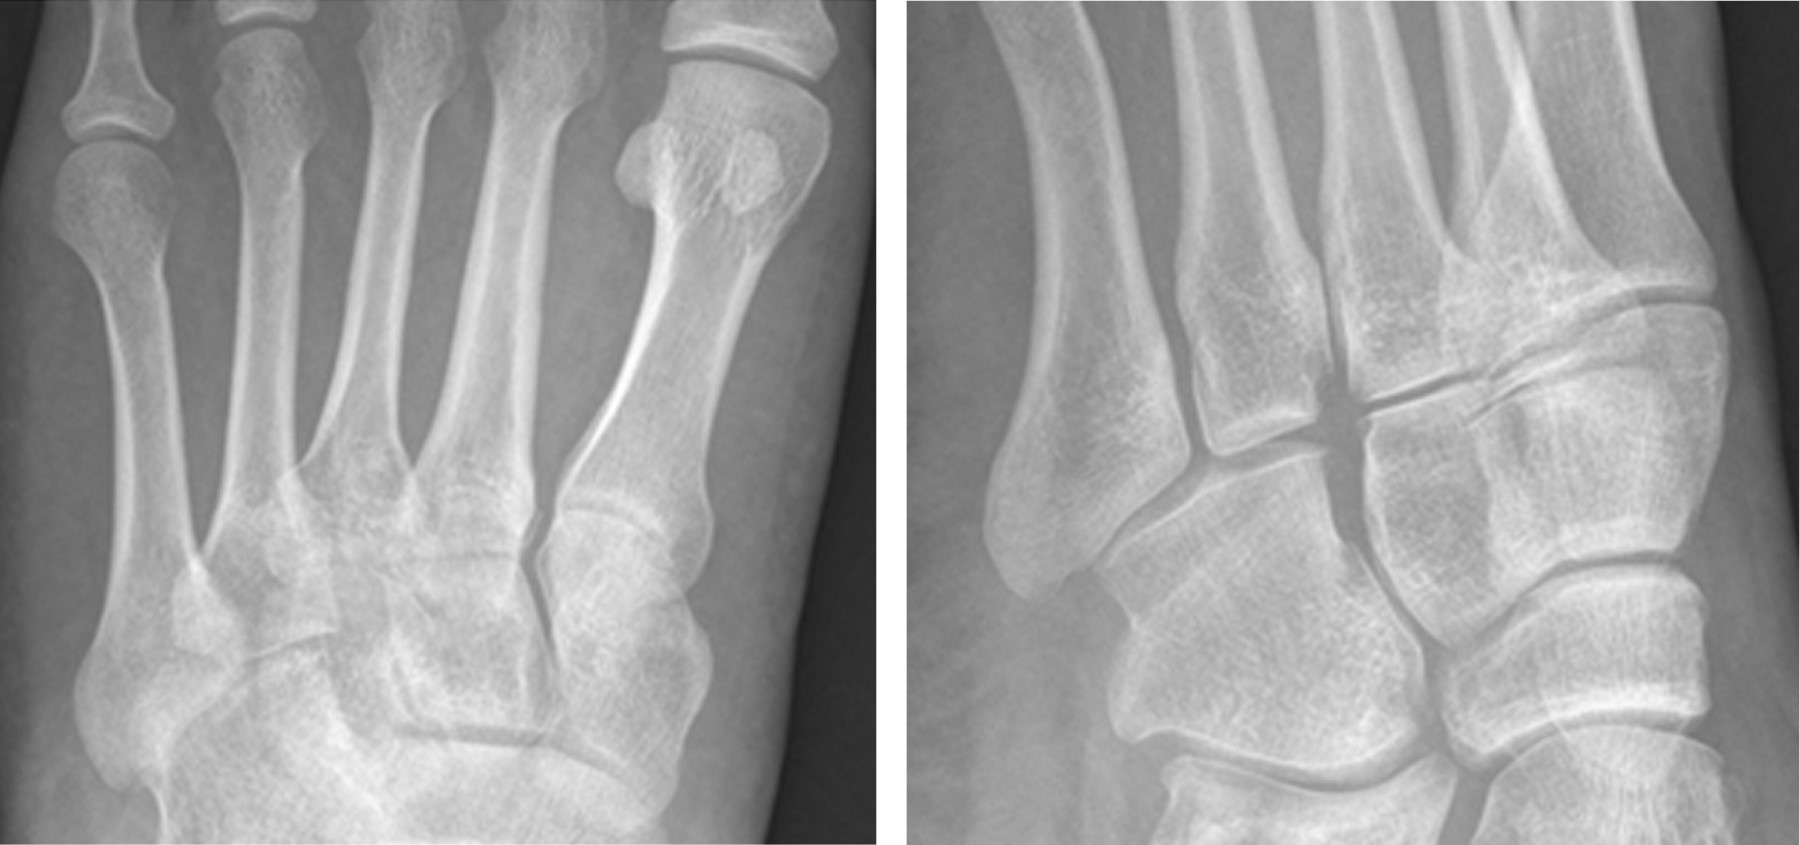

En cuanto al tipo de lesión, en el grupo de alta energía se observaron seis fracturas-luxación y una lesión ligamentosa pura. En el grupo de baja energía encontramos cuatro fracturas-luxación, una lesión ligamentosa pura y una lesión ósea pura (Figuras 1 y 2).

Figura 2